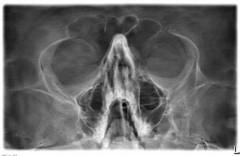

Диагностика искривлений носовой перегородки включает внешний осмотр, риноскопию и дополнительные анализы.

| Рентгенография черепа | * оценка состояния придаточных пазух; * выявление аномалий костей черепа; * выявление деформаций после травмы носа. | |